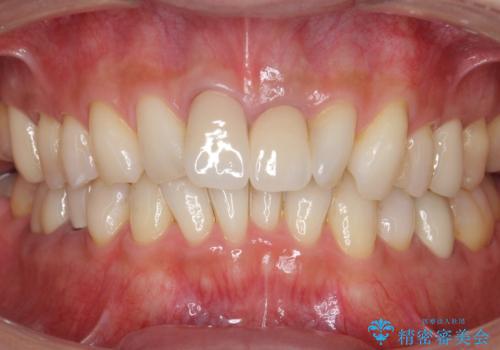

銀歯のやり替えと並行してホワイトニングも行いました。

結果的には銀歯がすべて白くなり、前歯のガタつきもある程度改善され大変喜んでいただけました。

治療終了時からナイトガードを使用していただき、歯ぎしりによる破折を予防しています。